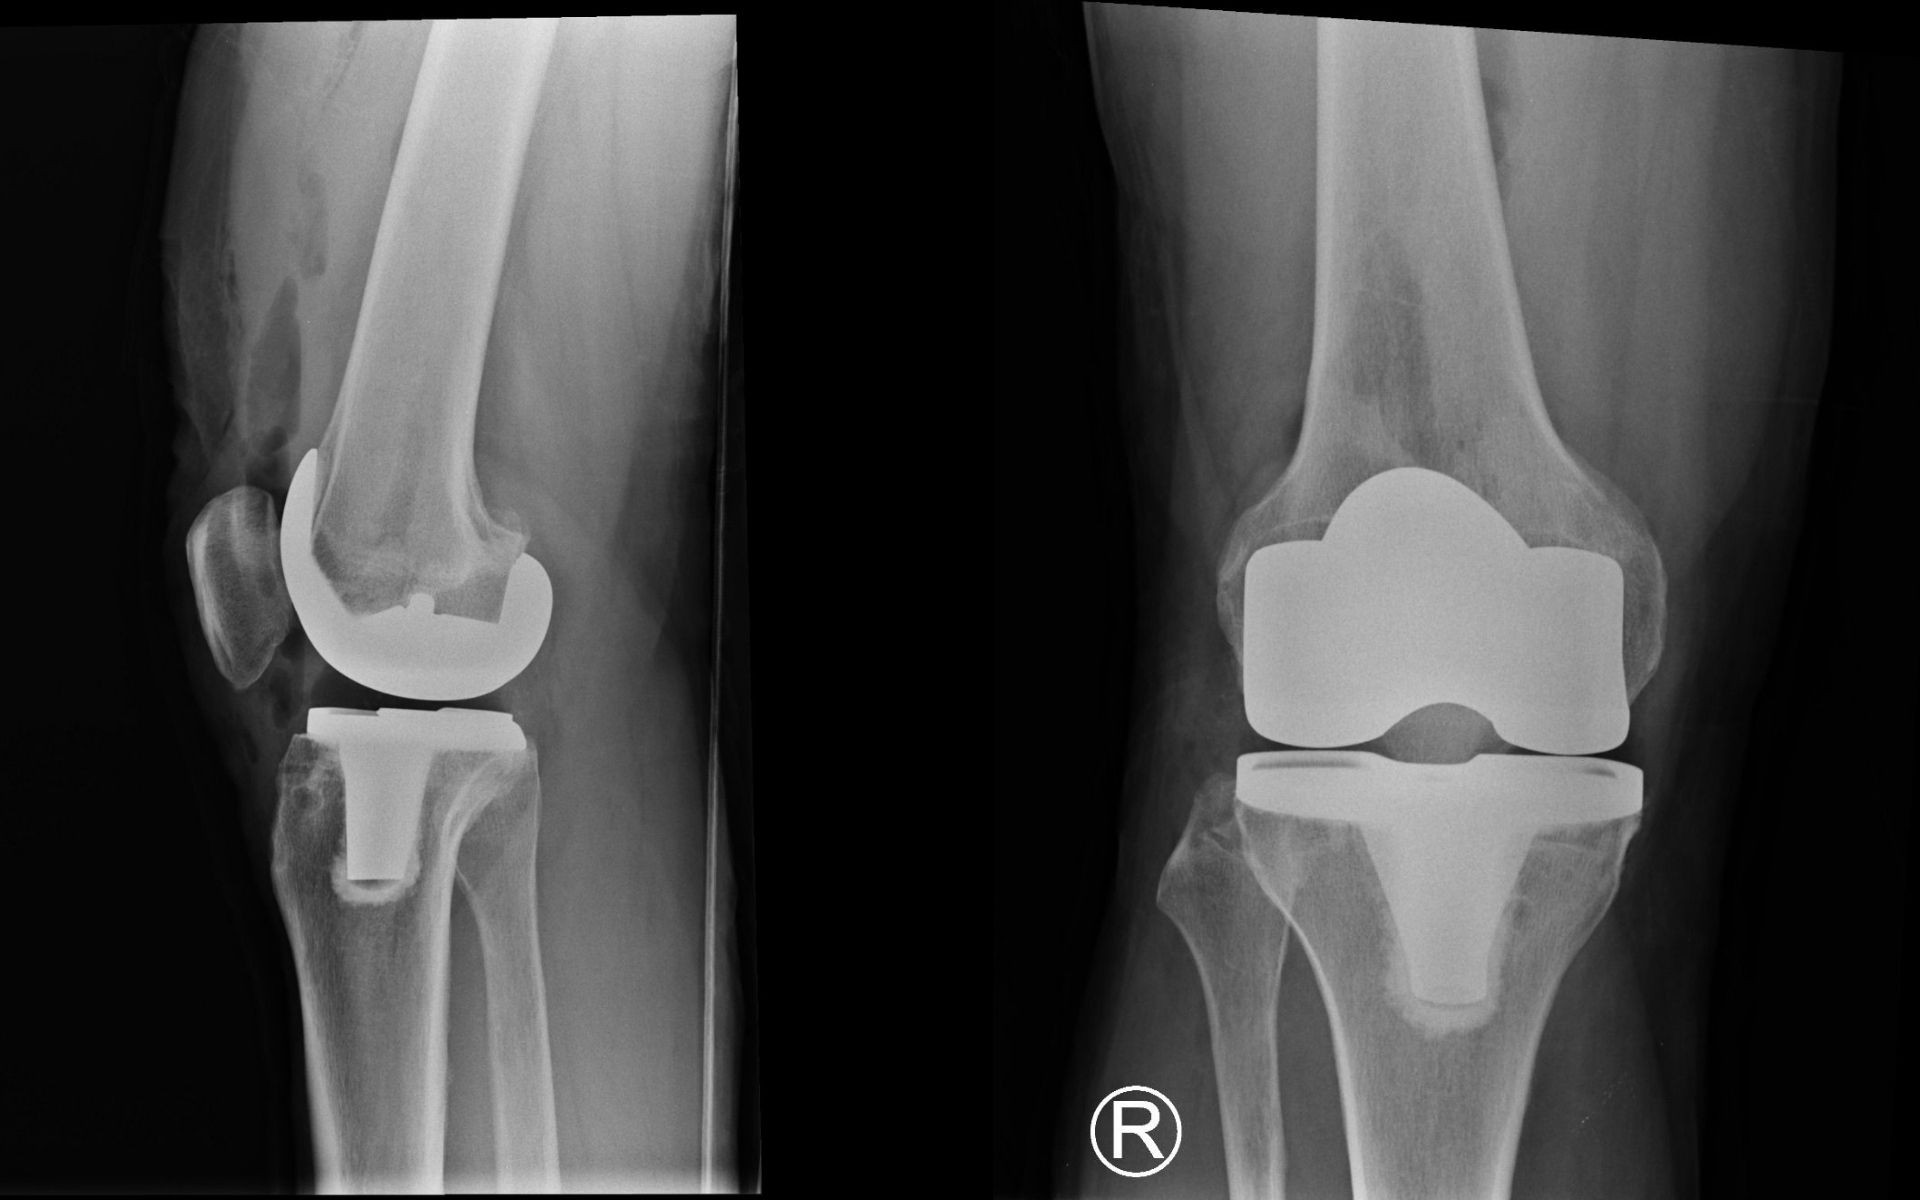

Setelah ketemu dr Theri, dan diskusi, diputuskan operasi 12 Desember. Theri juga sudah memilih merek dan tipe implant pada lutut saya nanti. Buatan Amerika. Saya tidak khawatir kalau usia implant itu hanya 25 tahun. Saya percaya, kelak akan ada teknologi yang lebih maju lagi!

Lutut kanan baru dengan implan dari Amerika.

Jadi memang sudah harus diganti. Kata Theri, implant saya size-nya paling besar. Karena tulang lutut saya besar. "Seharusnya sudah perfect", tegasnya.